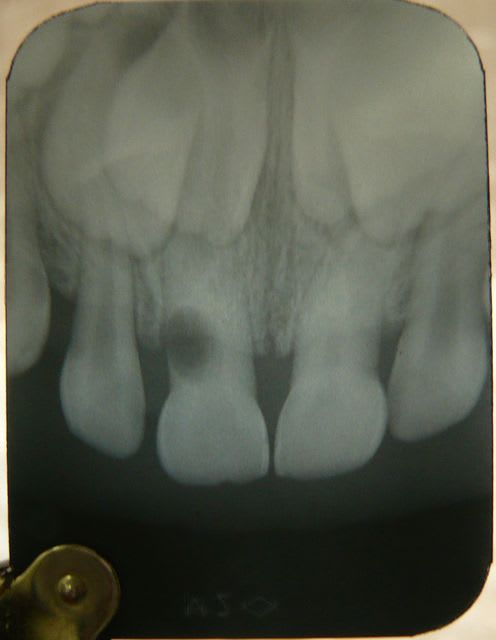

Voici un cas clinique de pédodontie:

Enfant de 4 ans et 7 mois.

Découverte fortuite lors du brossage par ses parents. Pas de douleurs signalées par l'enfant. Pas de souvenir de traumatisme pas de témoins mais l'enfant est un peu "cascadeur". Enfant en bonne santé générale.

Sur la radio, on observe une image de résorption latérale.

Pas de douleurs à la palpation ou au contact dentaire de la 51. Mobilité peut être un peu supérieure à la mobilité physiologique entre le pouce et l'index mais difficile a évaluer.

Quel est votre diagnostic? Quel traitement mettriez vous en place? quel est votre pronostic?